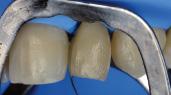

Composite Restorations in the Anterior Region

Restoring anterior teeth with large defects using composite seems to be quite challenging. With high-performance materials at hand and a systematic layering concept in mind, however, it is possible to produce highly aesthetic results in a reproducible way. The clinical case below is used to illustrate a dual-shade layering technique with CLEARFIL MAJESTY™ ES-2 Premium, a composite system with pre-defined colour combinations.

Case Example

The patient, a young male, was unhappy with the appearance of his maxillary anterior teeth. Several years ago, his central incisors had been restored with composite. These existing restorations had defective and heavily discoloured margins, while their shade did not match the adjacent natural tooth structure. The maxillary lateral incisors were peg-shaped (microdontia). Economic considerations and the desire to save as much natural tooth structure as possible made the team decide to restore all four maxillary incisors with composite. CLEARFIL MAJESTY™ ES-2 Premium became the material of choice as it eliminates the need for complicated shade combination formulas and supports predictable outcomes.

Restoring The Central Incisors

We decided to restore the central incisors first and then focus on the lateral incisors. The tooth shade was determined using the VITA™ classical A1-D4 shade guide, while composite buttons were applied to the teeth to verify the determined shade combination. In order to simplify the restoration procedure, a palatal silicon index was produced before removing the existing restorations.

An adhesive (CLEARFIL™ Universal Bond Quick) was applied after selective etching of the enamel to achieve a strong bond. With the aid of the silicon index, it was easy to create the palatal shells of the restorations with CLEARFIL MAJESTY™ ES-2 Premium in the shade A3E (enamel), which matches the determined tooth shade A3. The dentin core was built up with the same composite in the recommended shade A3D (dentin), mamelons were modelled and some CLEARFIL MAJESTY™ ES-2 Premium in the shade WD added for the incisal halo, while some individual effects (like enamel cracks) were imitated with brown stain. The build-up was finalized in the interproximal and labial areas with composite in the shade A3E. Between the central incisors, a wedge was used to retract the papilla and facilitate the designing of the interproximal contact area. The finished and pre-polished restorations already had a natural appearance.

Fig. 6 Situation after finalization of the central incisor restorations with composite in the enamel opacity.

Fig. 4 Light-cured palatal shells made of CLEARFIL MAJESTY™ ES-2 Premium in the shade A3E.

Fig. 7 Central incisor restorations after finishing and initial polishing.